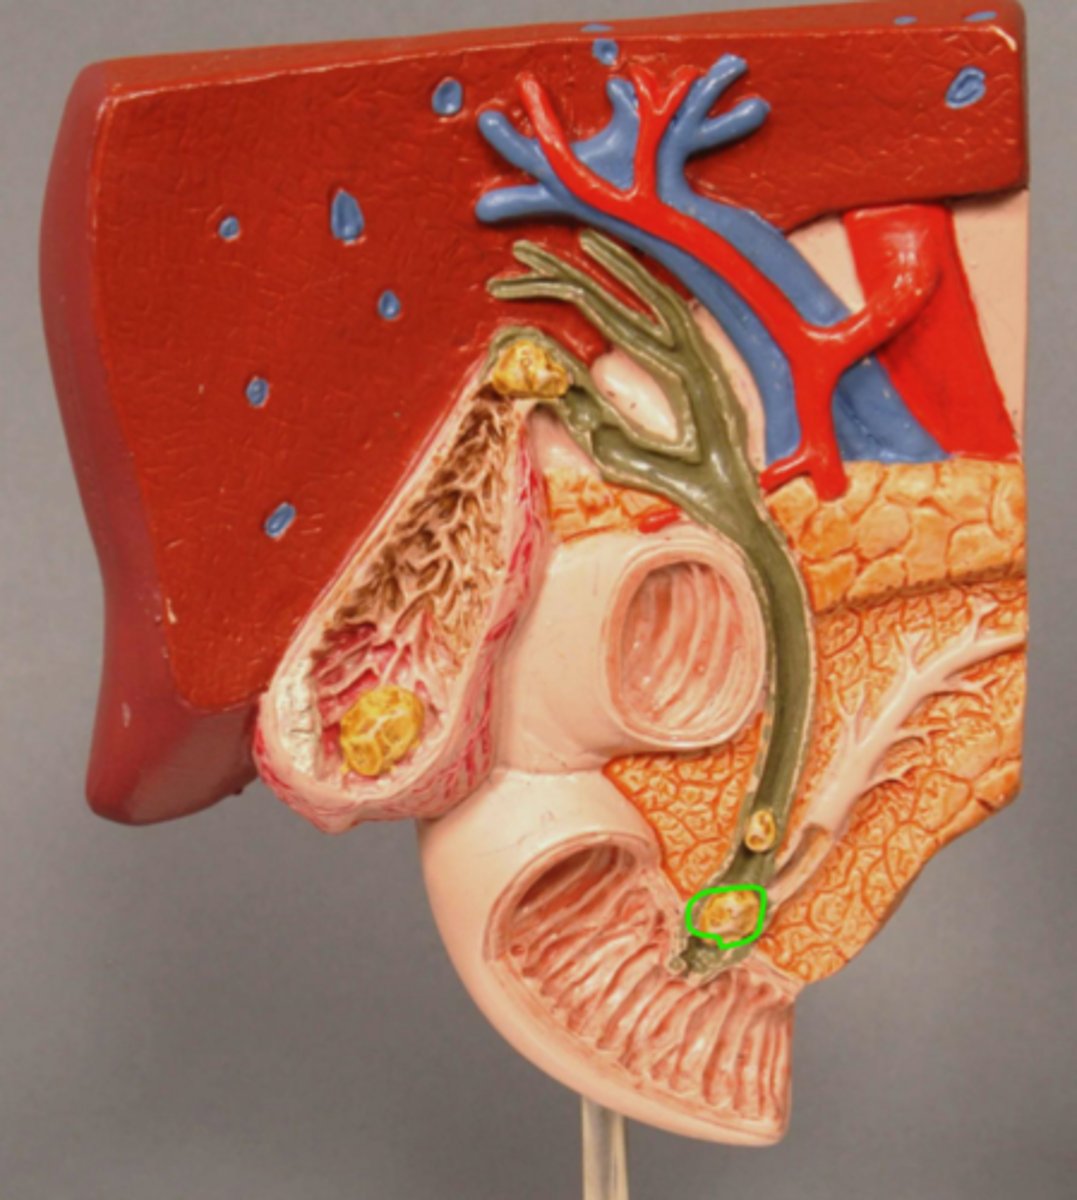

Gallstone Model

Gallstone in Bile Duct

Gallstone in Ampulla of Vater